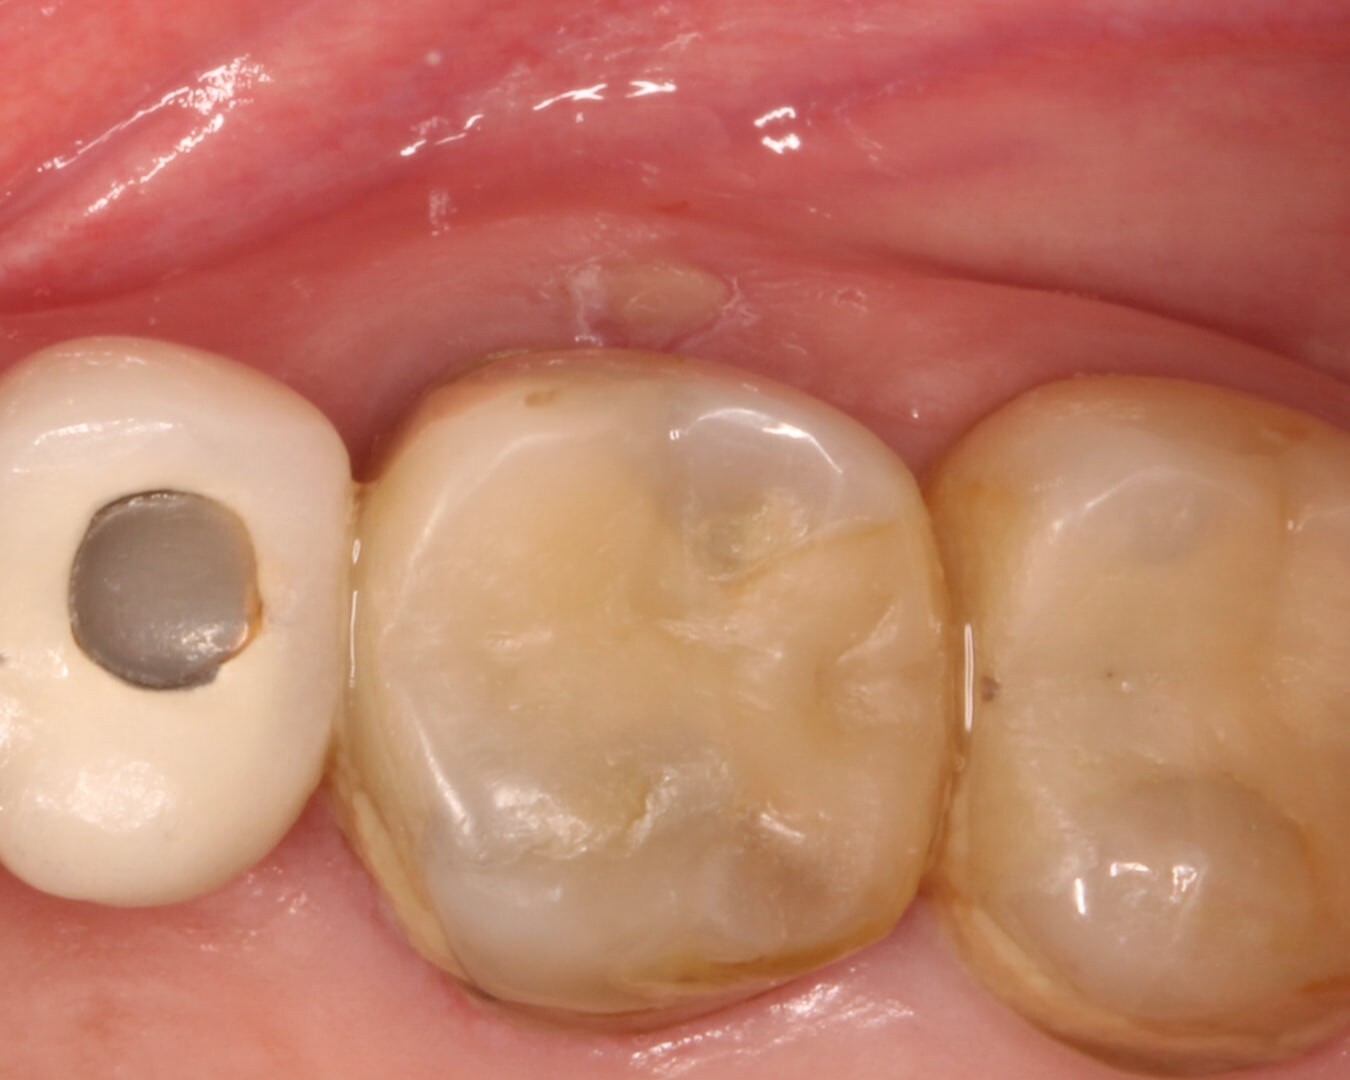

3. Через две недели свищевой ход закрылся. (Фото 6)